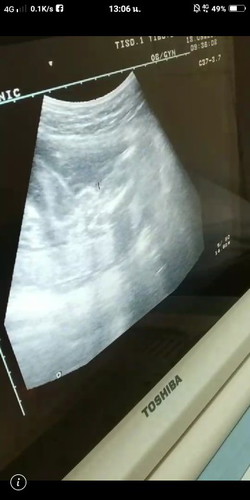

ซาวสองรอบแล้วหมอบอกยังไม่แน่หญิงหรือชาย 23w

ดูไม่ออกเลยค่ะ..ผู้หญิงหรือเปล่า